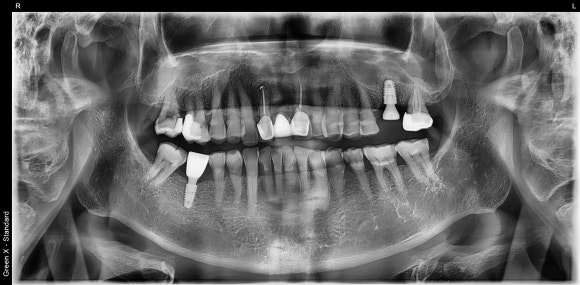

20250404

크라운을 붙인 날은 치료가 종료되는 날입니다.

엑스레이를 촬영해서 이물질이 남아있진 않은지 한 번 더 확인합니다.

![[임플란트] 이가 빠진지 오래되서 옆 치아들이 쓰러졌어요. 임플란트 가능할까요? 네, 가능합니다.1mm의 정교함으로! 관련 이미지 10](https://pub-9f2bb3498faf4d1d8714b41df24753e3.r2.dev/content/clinics/archive/nqmm0udu86/naver_blog/honeybeevuvu/assets/by_hash/bbd55c43b4118e2cbc7a7ab6dbe8dd57b082e06e2a954f7143a359322e389f98.jpg)

임플란트는 수술 과정이 정밀해야함은 물론이고,

치료가 종료된 후에도 섬세한 관찰이 필요합니다.

주기적인 스케일링과 임플란트 하방의 딥클리닝까지.

뭐든지 사후관리가 중요합니다.